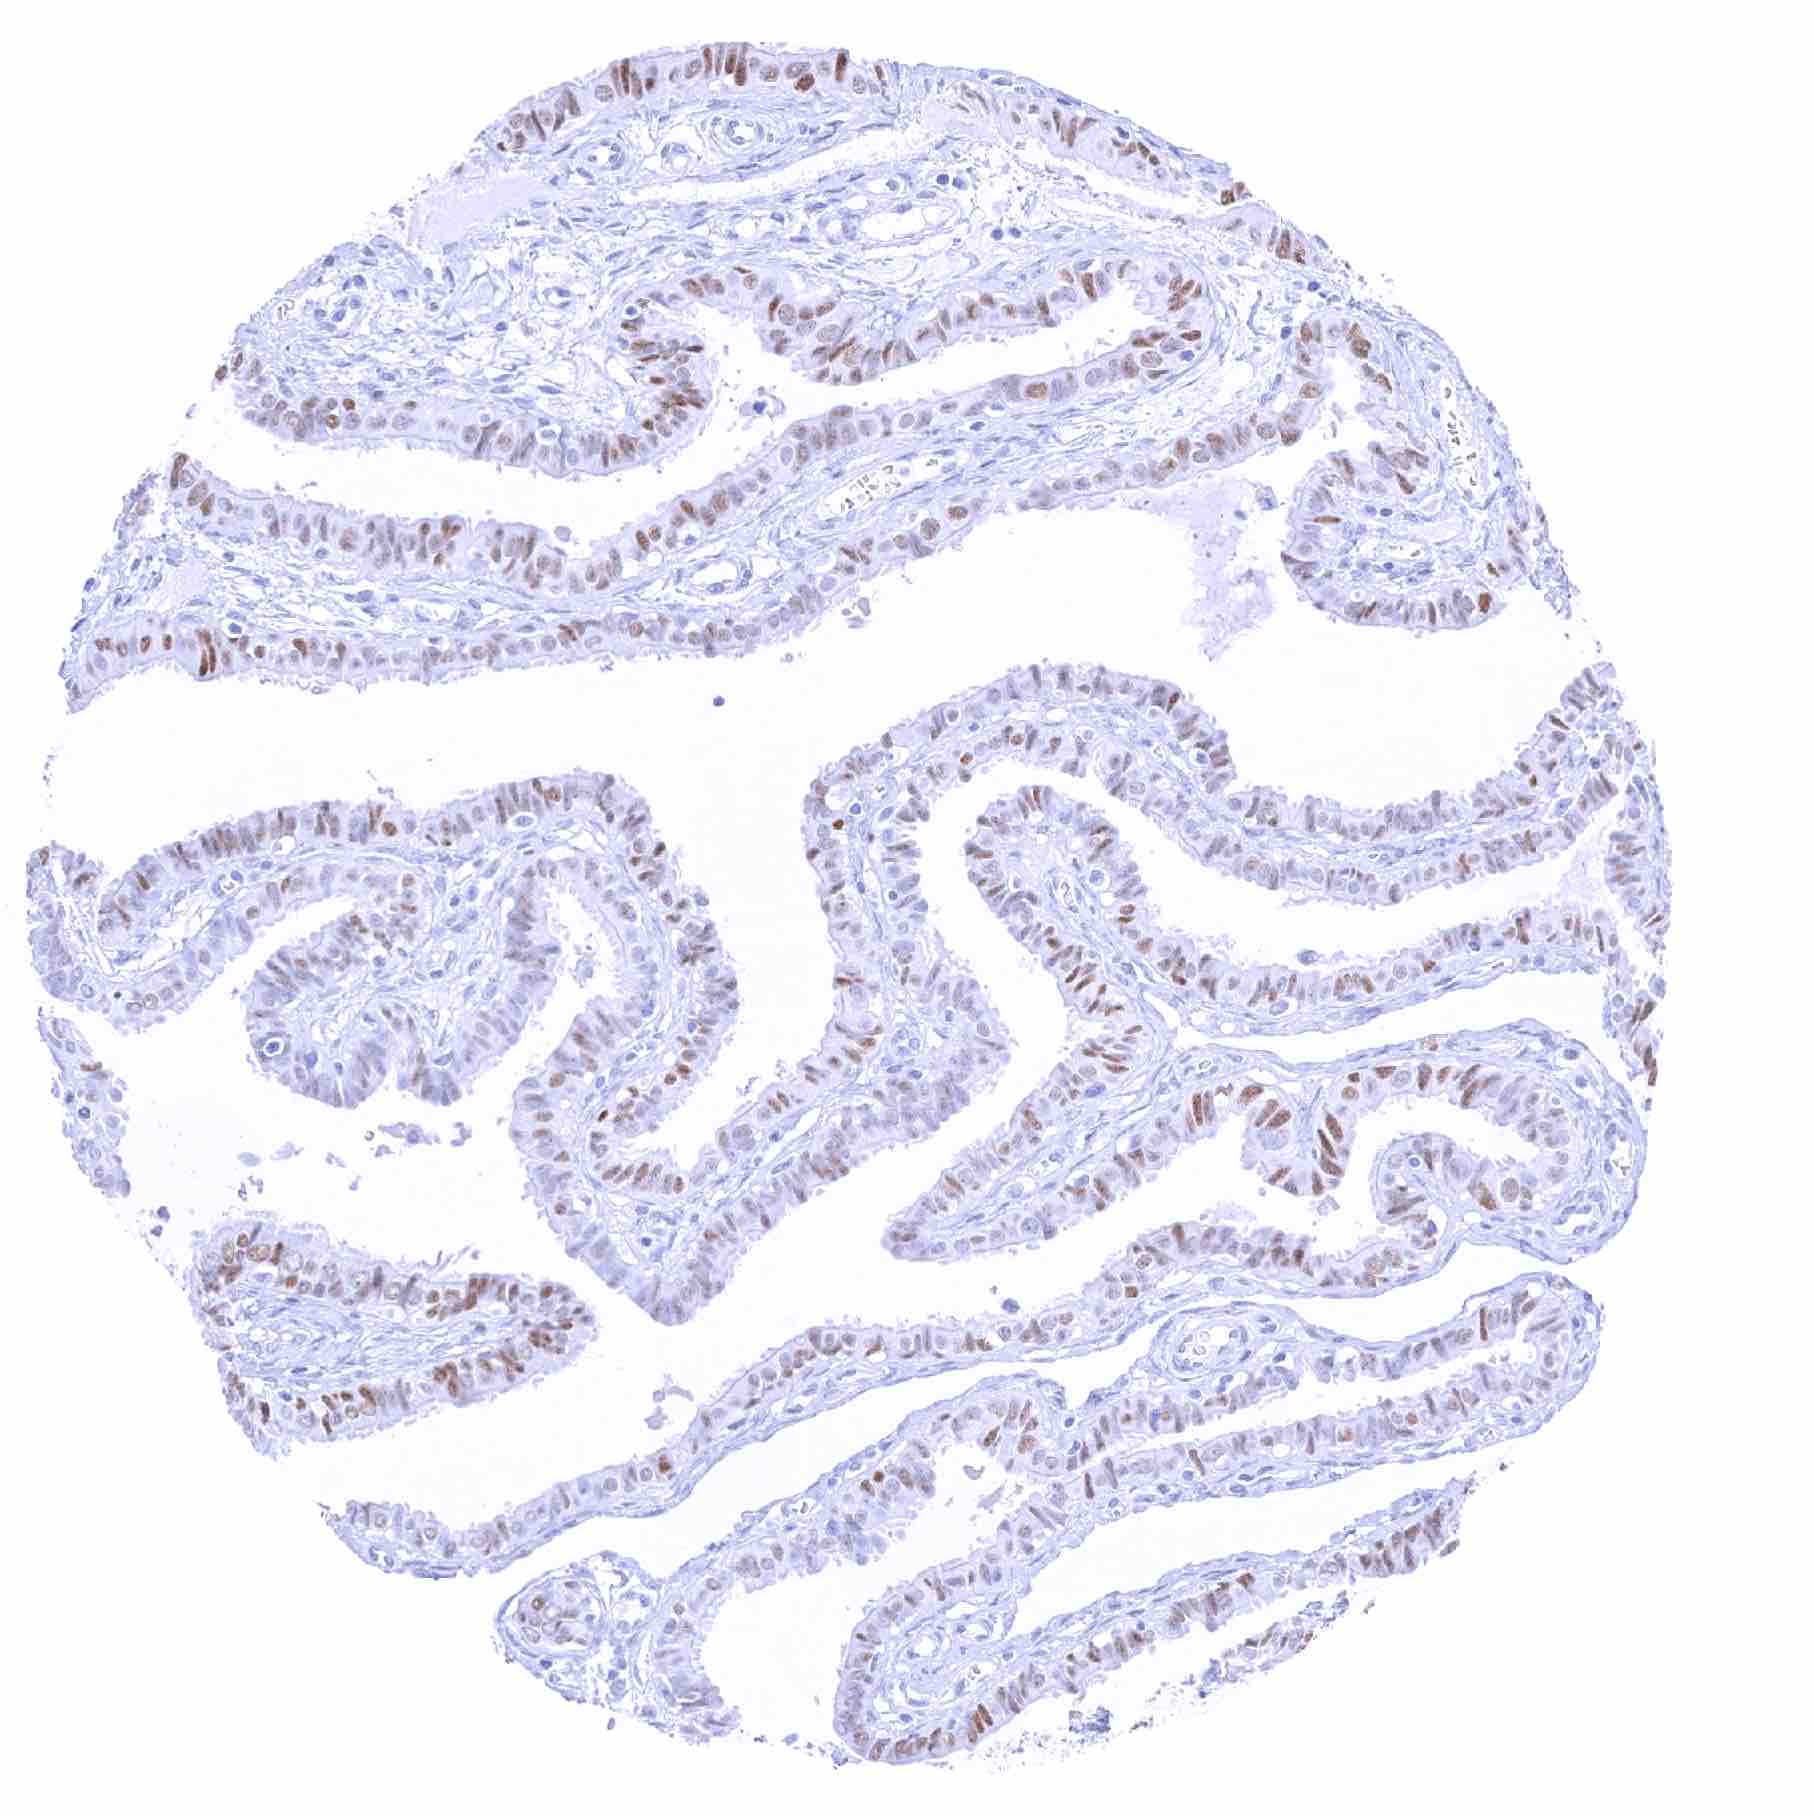

Fallopian tube, mucosa – Moderate to strong SOX2 positivity of a large subset of epithelial cells